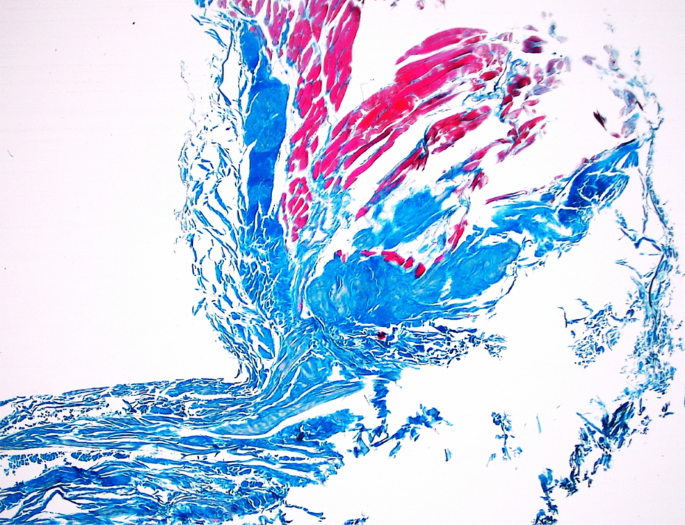

In histological terms, aponeurosis looks like a sheetlike fibrous membrane, histologically similar to tendon, where the parallel bundles of collagen exist as multiple layers alternating at 90° angles to one another. Our histological findings confirm that the fibre system correspond to an aponeurosis (Fig. 6.) The aponeurosis of the PPM differed significantly between different types of tendon, with regard to width at the beginning of the aponeurosis (p = 0.0001); width at the distal attachment (p = 0.0001); and thickness at distal attachment (p = 0.0106) (Supplementary Table 1).

Histological examination of the aponeurosis of the popliteus muscle—2 × magnification. The Fig. 6 was taken with Olympus EP50 camera (Olympus Corporation Japan).